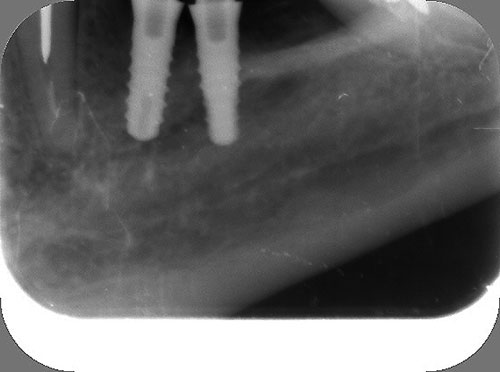

Mientras dichos movimientos ortopédicos se producen (período que supondrá otros seis meses), estudiamos los actos quirúrgicos a realizar en los cuatro implantes que pondremos. De acuerdo al estudio Desatascan realizado observamos tres situaciones diferentes: 1º-El Primer Molar Inferior Izquierdo, lo instalamos mediante Cirugía Minimamente Invasiva , con la aplicación de una Férula Quirúrgica Obtenida de los datos del scanner tratados con un programa de CMI (Cirugía Minimamente Invasiva), previa prueba en un modelo estereolitográfico, ya que la altura ósea era apenas de 9 mm. 2º- El Primer Molar Superior Derecho, se implantará mediante una ligera Elevación Atraumática (Trans alveolar) de Seno una vez logrado el espacio mesio distal necesario. 3º- El Incisivo Central Superior Derecho ausente, cuenta con un sustrato óseo prácticamente inexistente. El espesor de la tabla era de menos de 2 mm. Los caminos posibles a seguir para contar con una Rehabilitación de piezas independientes son dos: Optamos por esta segunda opción por ser menos cruenta y no necesitar de una zona dadora. Técnica esta que pondremos en práctica en dos etapas diferidas: 1º-Incisión horizontal palatinizada, incisiones peri rodetes gingivales e incisiones de descarga. Dilatación que comenzamos con dos incisiones de descarga sobre la cortical vestibular realizadas con disco. y el comienzo de la dilatación propiamente dicha mediante una hoja de bisturí, para luego seguir con un periostótomo . Recién después de alcanzada una cierta separación de la cortical vestibular de la palatina, empezamos con los dilatadores roscados. En este punto podríamos haber utilizado sin riesgos un Implante de 3,8 mm de diámetro, pero a fin de mejorar la estética del pilar emergente decidimos rellenar con material osteoconductor y osteoinductor (BiOss) y cubrir mediante membrana reabsorvible ( Bio Guide). 2º-Implantación seis meses después. Mientras se van cumpliendo los tiempos antes mencionados, y comprobamos reiteradamente la funcionalidad de la oclusión con los provisorios, tomamos impresiones definitivas y construimos primero el maxilar inferior, para definir en primer término la porción inferior de la Guía Anterior., y a nivel posterior Curvas y Microplanos. Para luego realizar los cuadrantes premolar- molar del superior: La espera de la regeneración ósea y sus tiempos pertinentes, más la espera de los tiempos de la implantación, nos obligaron a modificar las etapas del protocolo D.AT.O de manera de mantener la –D- mediante el sector superior de la GA. en provisorios, mientras fuimos resolviendo en forma definitiva los demás sectores. Ya pasados los meses necesarios para recrear un hueso adecuado en el área del Incisivo Superior Derecho, procedemos a resolver la implantación de dicha zona, observando que todo el esfuerzo dedicado al mismo había sido inútil, ya que la formación de hueso se produjo minimamente. Cuatro meses después tomamos impresiones del sector Antero Superior de la Guía Anterior, incluyendo el arrastre de un transfer . Seguimos modelando la encía con un nuevo juego de provisorios. Y se construye entonces el sector superior de la Guía Anterior. Se efectúa un control radiográfico a los 6 meses. Se ha intentado mostrar en esta Rehabilitación, que a pesar de las distintas circunstancias de cada paciente, siempre debemos tener en cuenta la necesidad de ejercer la DESOCLUSIÓN del caso como prioridad número uno, para luego perseguir la ALINEACIÓN TRIDIMENSIONAL de las arcadas y obtener así una OCLUSIÓN equilibrada. D.AT.O. ES EL PROTOCOLO QUE DEBEMOS SEGUIR EN TODA REHABILITACIÓN. BIBLIOGRAFÍA 1)William Mc Horris,B.S.,D.D.S. Oclusión. Con especial énfasis sobre :El rol funcional y parafuncional de los dientes anteriores. 2)Von Spee , Craff(Anatomista alemán, describió la curva de compensación de la articulación de molares y premolares).CURVA DE SPEE 1.89 3)Stuart,D.”Some aspects of the inervation teeth.”Procedings of Royal Society of Medicine.20:1675,19274)Muhleman,H. y Savdir,S”Tooth movility-its causes and significance”Journal of Periodontology ,36:153,Marzo ,Abril,1965. 4)Muhleman,H. Y Savdir,S”Toothmovility its causes and significance” Journal of Periodontology,36:153,marzo,abril,1965. 5-Oclusión y Diagnóstico en Rehabilitación Oral. 6-Anatomia Odontológica. 7-A contribution to the study of the movementes of the mandible. 8-Celenza F.W, Nadeskin J.F.,Oclusión.Situación actual. 9-D´Amico 10-Dawson P.E. 11-Huffman –Regenos. 12-Hobo S.-Takayama H.A. 13-Lucia V.O 14-Mc Horris. 15-Mc Horris. 16-Stuart C. 17-Vartan Veshnilian 18-Alvarez Cantoni H. AUTOR:Ratificación del Protocolo en Rehabilitación Bucal a pesar de las incidencias propias de cada caso clínico. A propósito de un caso.

Se utilizarán dos Implantes roscados de 8 mm de longitud por 3,8 mm de ancho.

El implante se encontraba perfectamente según comprobaciones radiográficas y clínicas al sondeo.